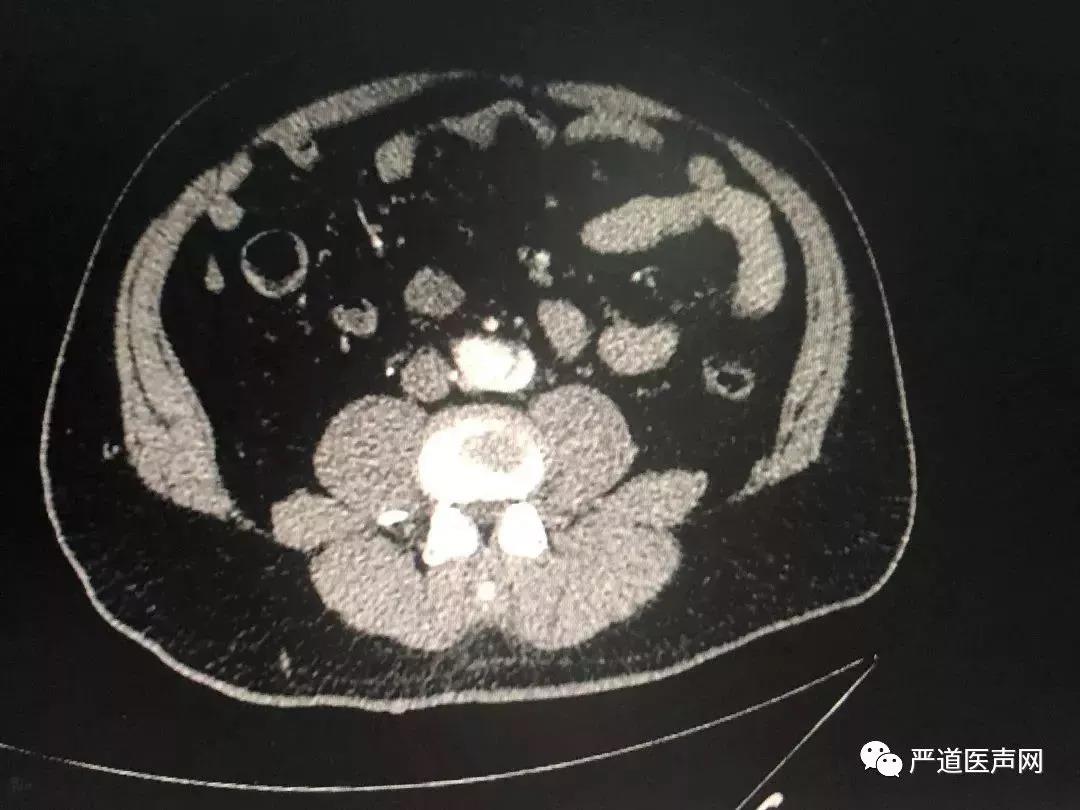

四、冠状动脉CTA检查

考虑到主动脉夹层可能,经猪尾导管行主动脉造影不安全,接下来完成了主动脉CTA检查:

▲主动脉CT提示:自升主动脉根部开始至腹主动脉分出髂动脉之前全段夹层形成

至此,患者胸背痛的原因基本明确:1型主动脉夹层